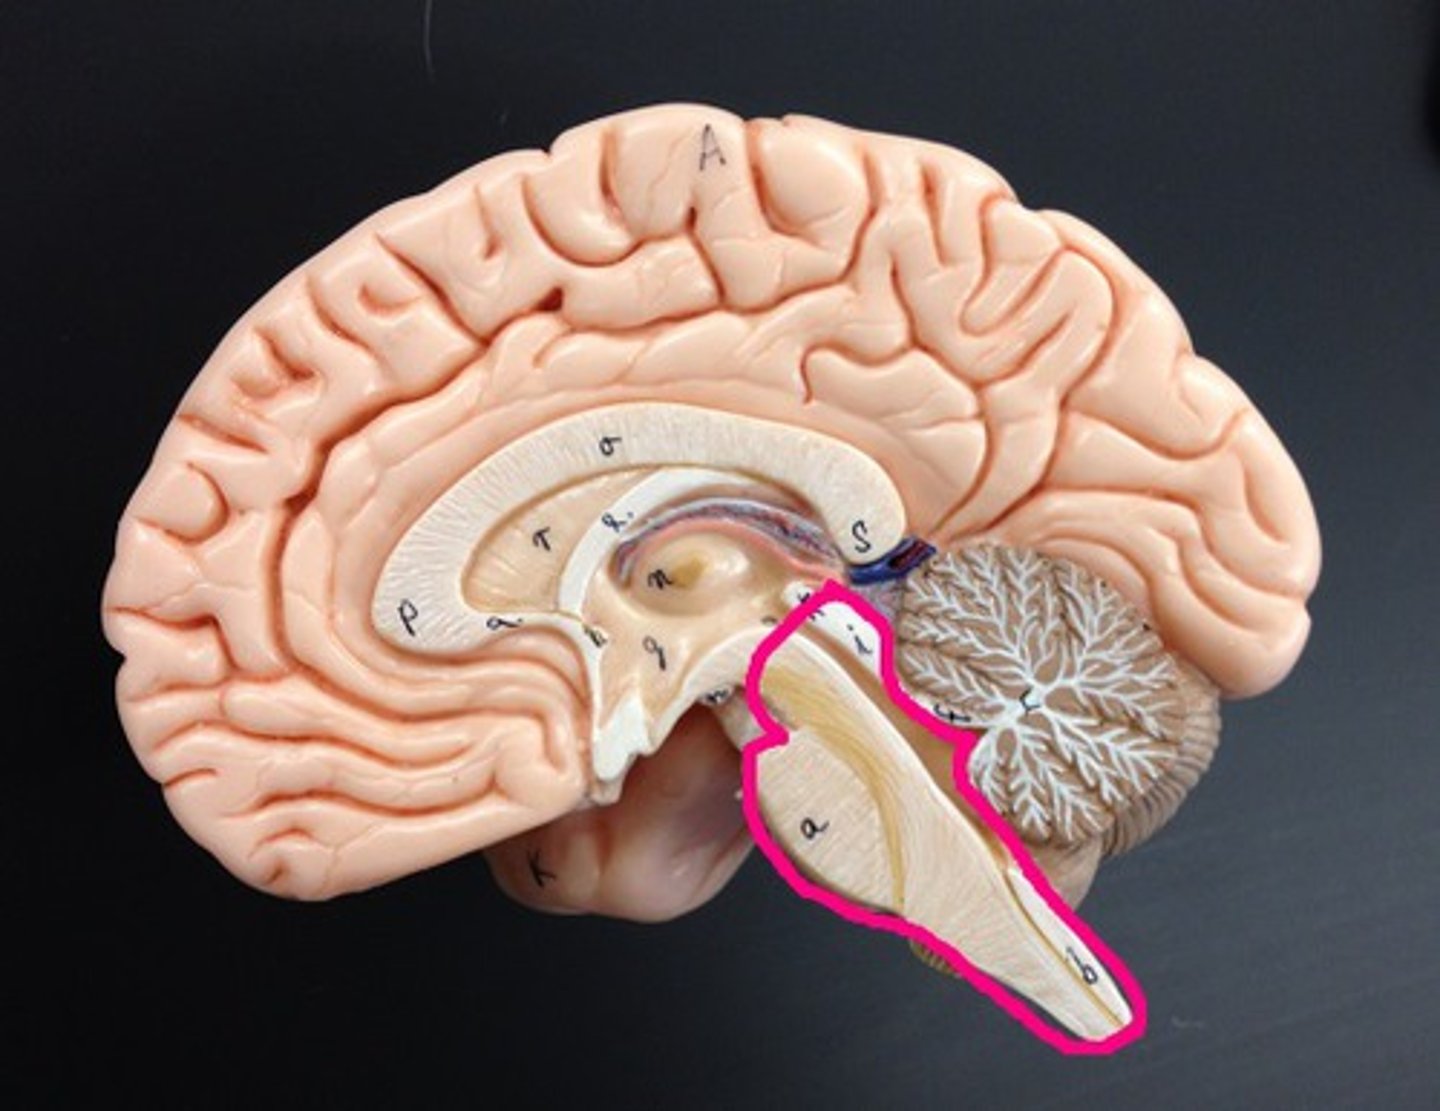

Cerebellum

Two hemispheres with convoluted surfaces,

Accounts for ~11% of total brain mass,

Provides involuntary coordination of body movements,

Also plays a role in posture and equilibrium

Cerebellum involuntary coordination

1) Receives input from motor cortex, brain stem (relays info from cortex), and sensory receptors to provide precise timing and appropriate patterns of skeletal muscle contraction,

2) Results in smooth, coordinated movements and agility (driving, walking, typing, etc.),

3) Completely subconscious (have no awareness of its functioning)

4th Ventricle